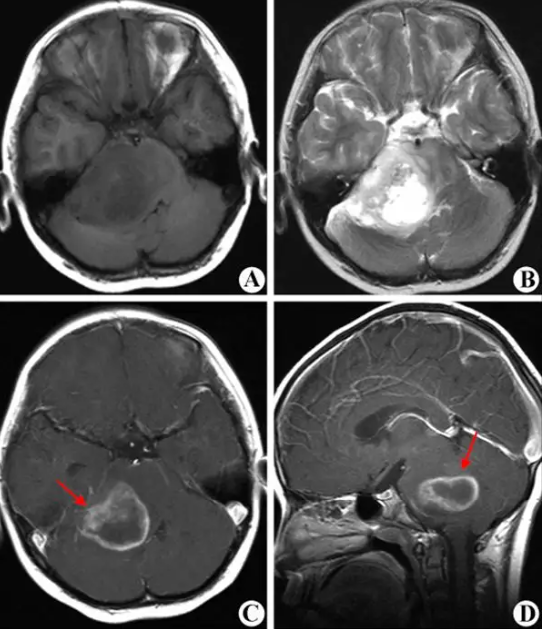

• 9岁女孩髓母细胞瘤切除术后案例【髓母细胞瘤切

9岁女孩髓母细胞瘤切除术后案例【髓母细胞瘤切

内容简介: 患者档案:性别:女就诊年龄:9岁(当时)病名:髓母细胞瘤切除术后病理诊断:经典型髓母细胞瘤(CNS WHO Ⅳ级),非 WNT 非 SHH 型,

详细资料 9岁女孩髓母细胞瘤切除术后案例【髓母细胞瘤切